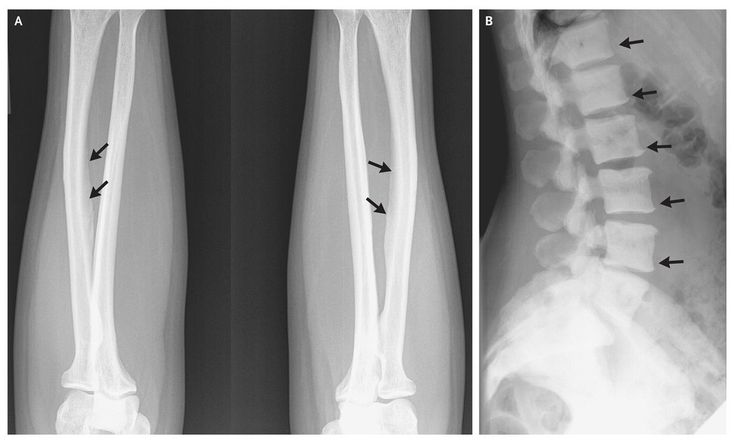

A 47-year-old woman was referred for bone pain and abnormal findings on radiography. The patient reported that for the past 17 years, she has habitually consumed a pitcher of tea made from 100 to 150 tea bags daily (estimated fluoride intake, >20 mg per day). She reported a 5-year history of pain in the lower back, arms, legs, and hips. Because of brittleness, all her teeth had been extracted. Radiography of the forearm revealed interosseous membrane calcifications (Panel A, arrows), and radiography of the spine revealed a rugger-jersey appearance (striated pattern of increased density in the upper and lower zones of the vertebrae) (Panel B, arrows), suggesting skeletal fluorosis. The serum fluoride concentration was 0.43 mg per liter (23 μmol per liter; normal concentration, <0.10 mg per liter [5 μmol per liter]). Skeletal fluorosis is endemic in areas with high concentrations of fluoride in the drinking water, but it is rare in other parts of the world. Brewed tea has one of the highest fluoride contents among beverages in the United States. After appropriate counseling, the patient discontinued tea consumption, with improvement in her symptoms. Since it can take years to deplete skeletal fluoride, we are considering whether to increase bone remodeling with the intermittent use of teriparatide to facilitate the elimination of skeletal fluoride.